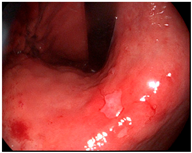

After surgery, we immediately evaluated the surgical specimen and performed back-table dissection. Lymph node-bearing adipose tissue was separated from the gastric specimen according to the anatomical definitions of the Japanese classification of gastric carcinoma [26]. Lymph node-bearing adipose tissue was additionally evaluated using NIR fluorescence imaging for the separation of lymph nodes and basins, as previously described [14]. The gastric wall was opened along the greater or lesser curvature on the opposite side of the lesion for gross inspection. The resected stomach dimensions and extent of NIR fluorescence signal were measured (Figure 3). The long axis and orthogonal length of the ICG diffusion range were measured on both the mucosal and serosal sides of the gastric wall. Tumor size and length of the proximal or distal resection margin were measured and recorded.

Figure 3.

Specimen examination: measurement of the fluorescent diffusion range on a gastric specimen. (left) mucosal side; (right) serosal side.